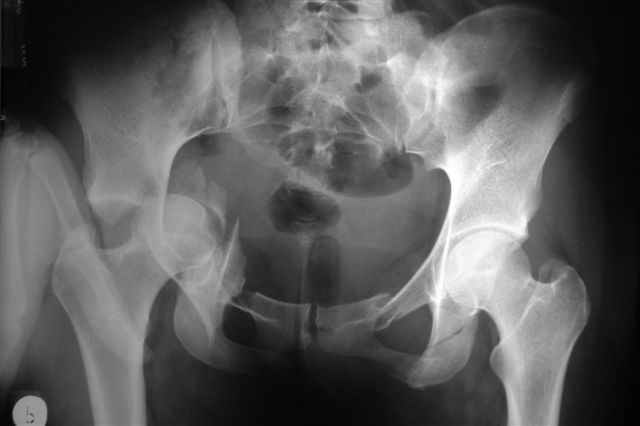

Трудности возникли сразу после рассечения большой ягодичной мыцы - короткие наружные ротаторы едва ли определялись - головка и шейка (как видно на

снимке) ушли в таз, пришлось воспользоваться дистрактором( ручные попытки выдернуть голову из под проксимального фрагмента - безуспешны) Шарнирный дистрактор - великое изобретение, без него репозиция была просто невозможна.

P.S. в приложении R пациентки с похожей проблемой доступа.. за исключением того, что перелом

двухколонный. Вертлугу лечили Y доступом.